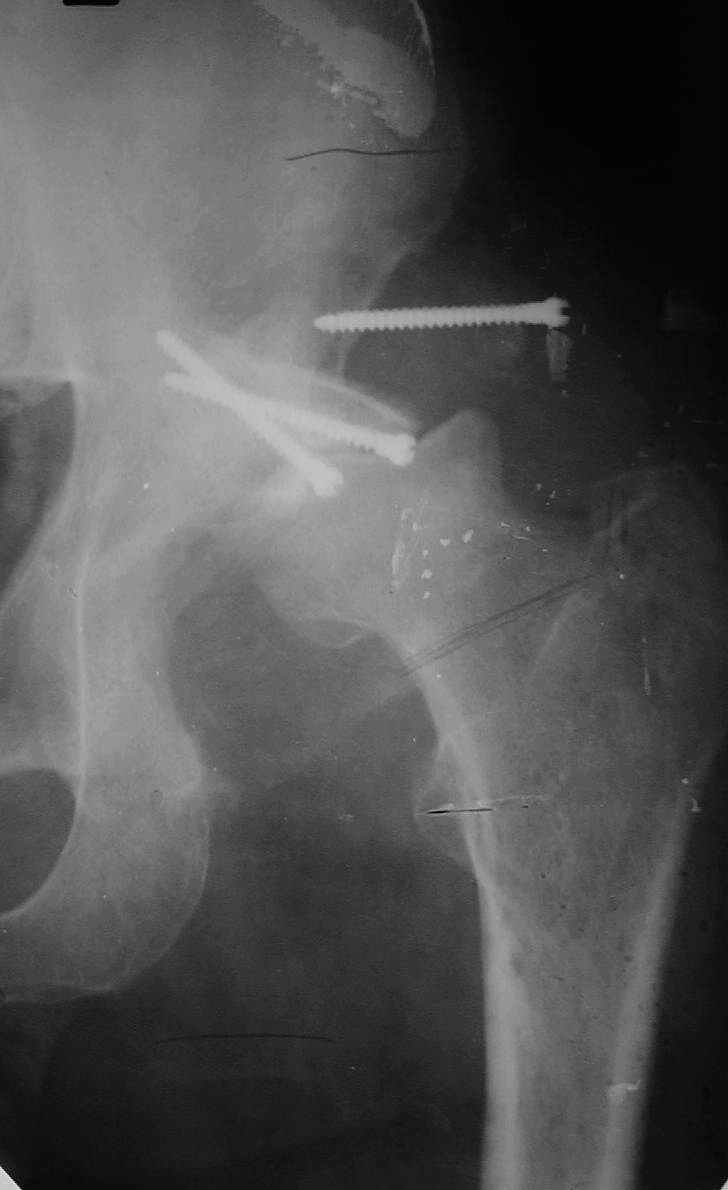

В институте совместно с фирмой Зиммер достаточно регулярно (практически ежемесячно) проводятся 2-х недельные циклы по различным вопросам эндопротезирования. Если есть возможность и желание, мы готовы поделиться с Вами нашим опытом, тем более есть что показать и что обсудить - в настоящее время ежедневно выполняется от 6 до 10 эндопротезирований коленного и тазобедренного сустава. В качестве примеров хочу показать 2 наблюдения, через 1 год и 5 лет после операции

5 лет